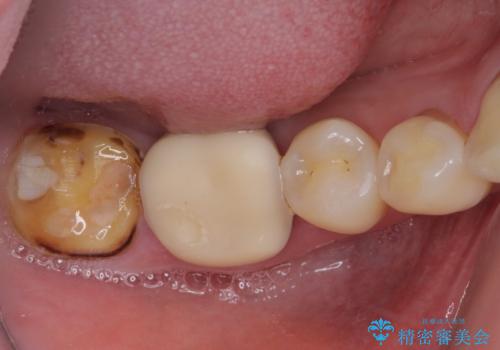

奥歯の壊れたり汚れたりしたクラウン オールセラミッククラウンによる審美歯科治療